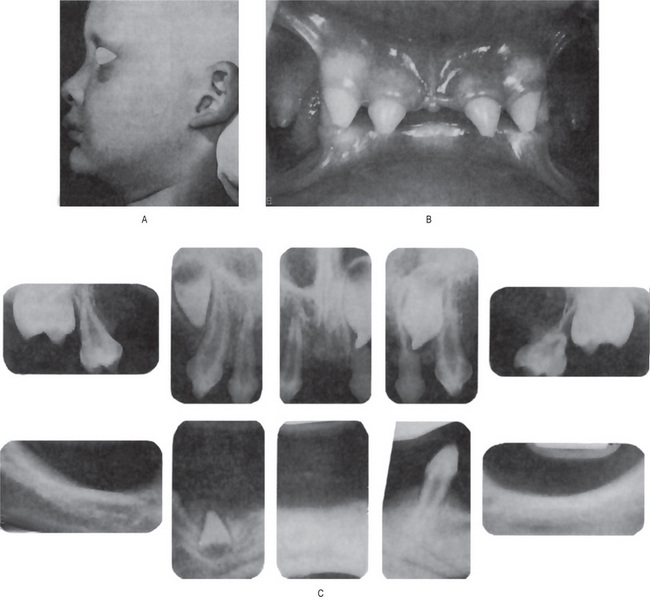

Figure 19-1 Hereditary ectodermal dysplasia.

(A)The protuberant lips, the thin, scanty hair and the saddle-nose are characteristic of the disease. (B) The teeth are cone-shaped. (C) Radiographs showing congenitally missing teeth Courtesy of Dr Ralph E McDonald.

Figure 19-2 Ectodermal dysplasia.

(A) Lateral view showing frontal bossing, collapse of the middle third face, and sparse hair on the scalp. (B) Intraoral view showing peg-shaped incisors Courtesy of the Department of Oral Pathology and Microbiology, KLE's Institute of Dental Sciences, Belgaum.

The oral findings are of particular interest, since patients with this abnormality invariably manifest anodontia or oligodontia, complete or partial absence of teeth, with frequent malformation of any teeth present, both deciduous and permanent dentitions (Fig. 19-1B and C). Where some teeth are present, they are commonly truncated or cone shaped. It should be pointed out that even when complete anodontia exists, the growth of the jaw is not impaired. This would imply that the development of the jaws, except for the alveolar process, is not dependent upon the presence of teeth. However, since the alveolar process does not develop in the absence of teeth, there is a reduction from the normal vertical dimension resulting in the protuberant lips. In addition, the palatal arch is frequently high and a cleft palate may be present (Fig. 19-2).